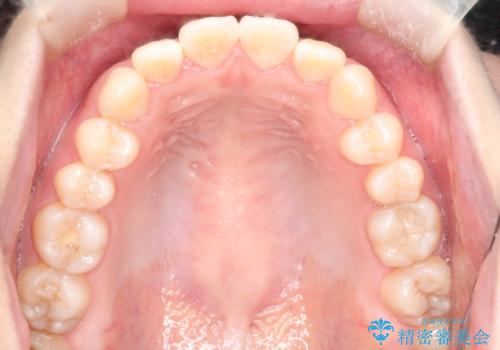

- 20代女性

- 矯正装置

- 審美装置

- ”口元を下げたい”が主訴で来院されました。

抜歯してワイヤー矯正を行い、口元も改善され大変満足していただきました。

小臼歯の抜歯を行うことで口元を改善することができました。